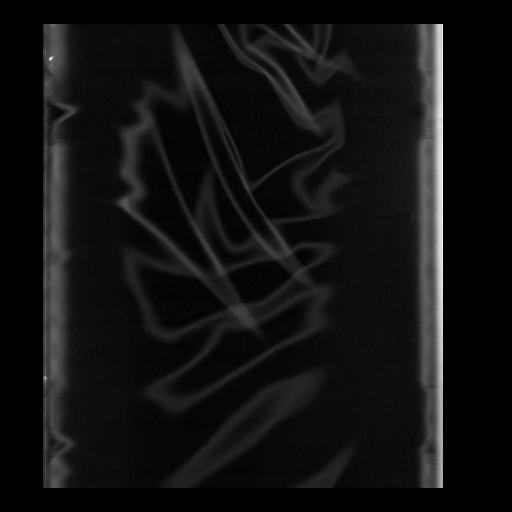

35 CUERPO,CE,Coronal,3.000,CUERPO,Coronal,